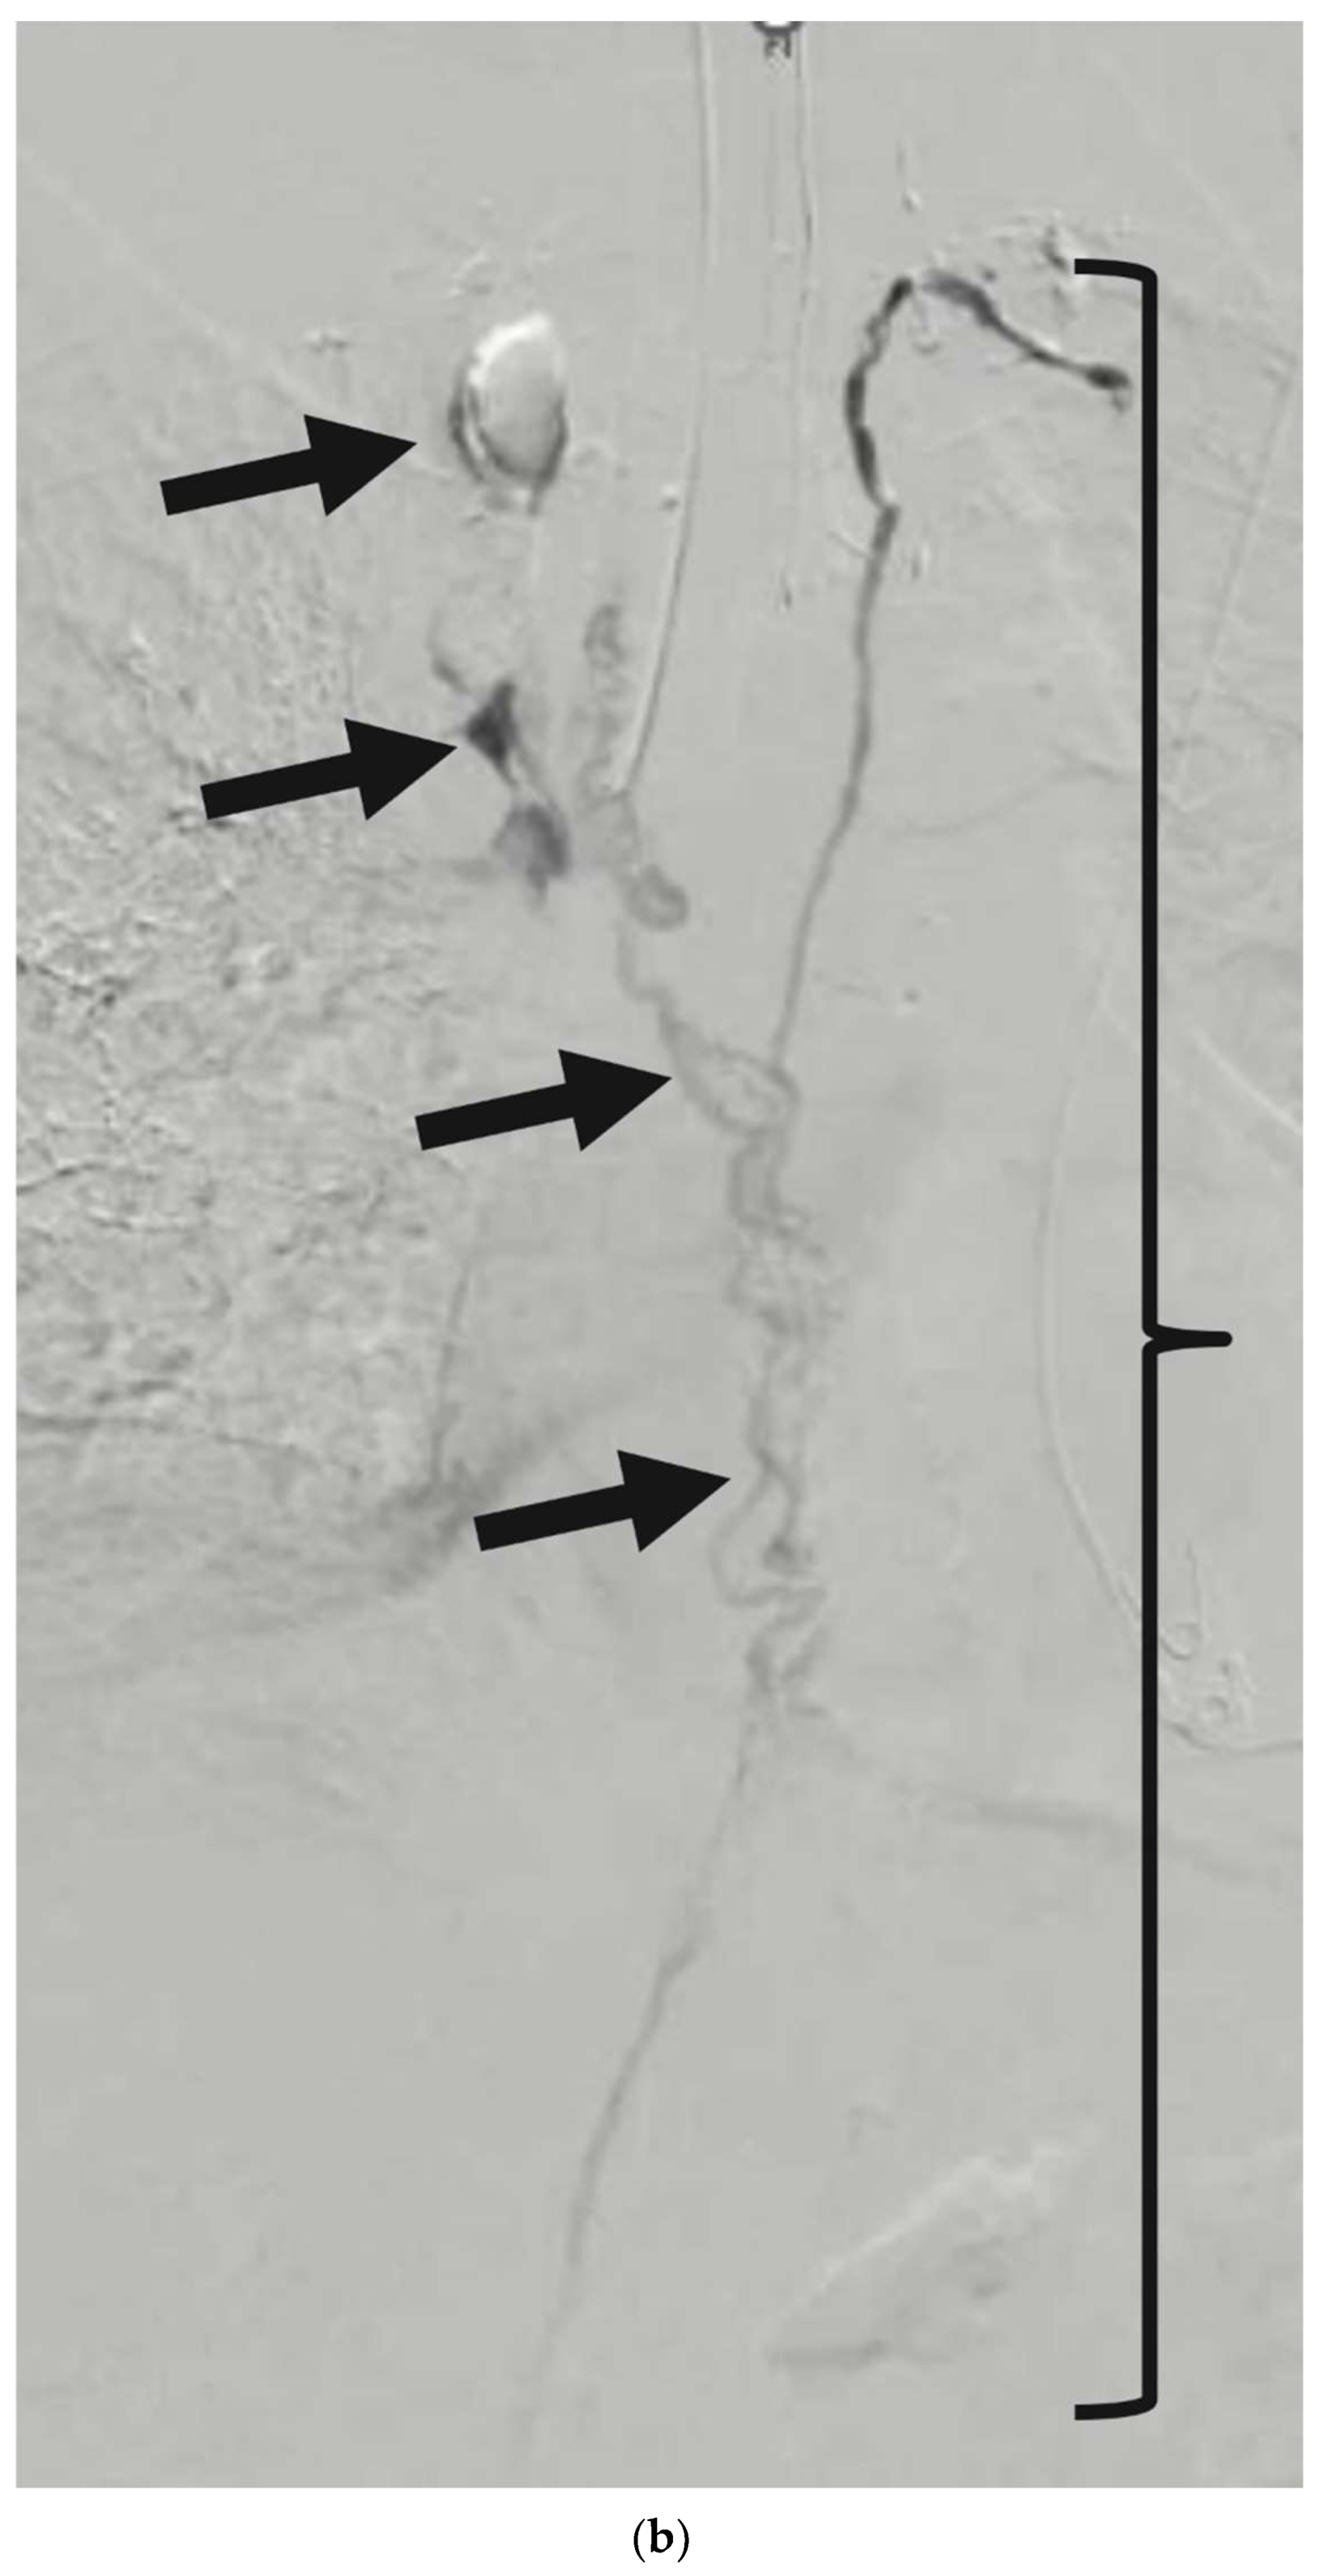

Figure 5. (a) Antero-posterior fluoroscopic lymphangiogram of a 34-day-old neonate with congenital chylothorax. Black arrows demonstrate a preferential flow through the dermal lymphatics without filling of the central conducting lymphatics, which would be expected over the midline of the spine, consistent with a central conducting lymphatic anomaly (CCLA). (b) is a coronal 3D reformat from cone-beam CT images. The white arrows correspond to dermal lymphatics without lymphatic channels in the central midline.